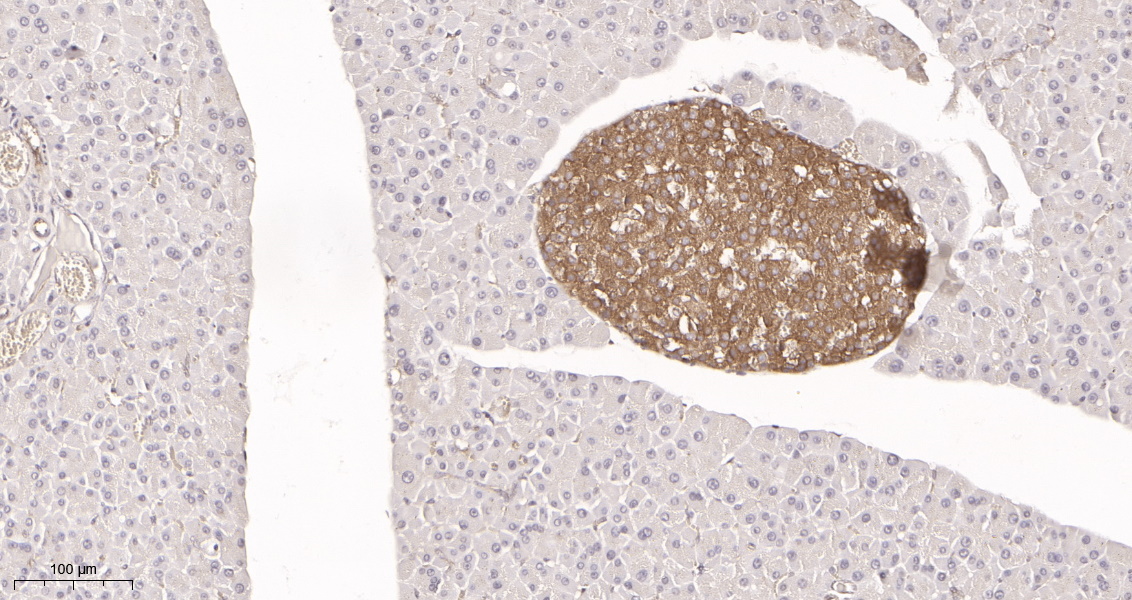

产品名称DRP1 (5F8) Rabbit Monoclonal Antibody

推荐应用WB,IHC-P,IF-P,IF-F,IF-ICC,IP,ELISA

稀释度IHC-P 1:200-1000,WB 1:1000-5000,IF-P/IF-F/IF-ICC 1:200-1000,ELISA 1:5000-20000,IP 1:50-200

背景介绍This gene encodes a member of the dynamin superfamily of GTPases. The encoded protein mediates mitochondrial and peroxisomal division, and is involved in developmentally regulated apoptosis and programmed necrosis. Dysfunction of this gene is implicated in several neurological disorders, including Alzheimer's disease. Mutations in this gene are associated with the autosomal dominant disorder, encephalopathy, lethal, due to defective mitochondrial and peroxisomal fission (EMPF). Alternative splicing results in multiple transcript variants encoding different isoforms. [provided by RefSeq, Jun 2013].

功能catalytic activity:GTP + H(2)O = GDP + phosphate.,function:Functions in mitochondrial and peroxisomal division probably by regulating membrane fission. Enzyme hydrolyzing GTP that oligomerizes to form ring-like structures and is able to remodel membranes. May also play a role on organelles of the secretory pathway.,miscellaneous:Isoform 1 and isoform 2 inhibits peroxisomal division when overexpressed while isoform 3 and isoform 4 have no effect.,PTM:Phosphorylated by GSK3B.,similarity:Belongs to the dynamin family.,similarity:Contains 1 GED domain.,subcellular location:Mainly cytosolic. Also membrane-associated. Localizes to mitochondria at spots of division events. Associated with peroxisomal membranes, it is recruited in part by PEX11B. May also be associated with endoplasmic reticulum tubules and cytoplasmic vesicles and found to be perinuclear.,subunit:Homotetramer; N-terminal part binds to the C-terminal part of another DNM1L. Can self-assemble in multimeric ring-like structures. Interacts with FIS1 (By similarity). Interacts with GSK3B.,tissue specificity:Ubiquitously expressed with highest levels found in skeletal muscles, heart, kidney and brain. Isoform 1 is brain-specific while isoform 3 and isoform 4 are predominantly expressed in testis and skeletal muscles respectively. Isoform 2 is weakly expressed in brain, heart and kidney and isoform 5 is dominantly expressed in liver, heart and kidney.